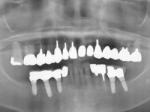

術前レントゲン